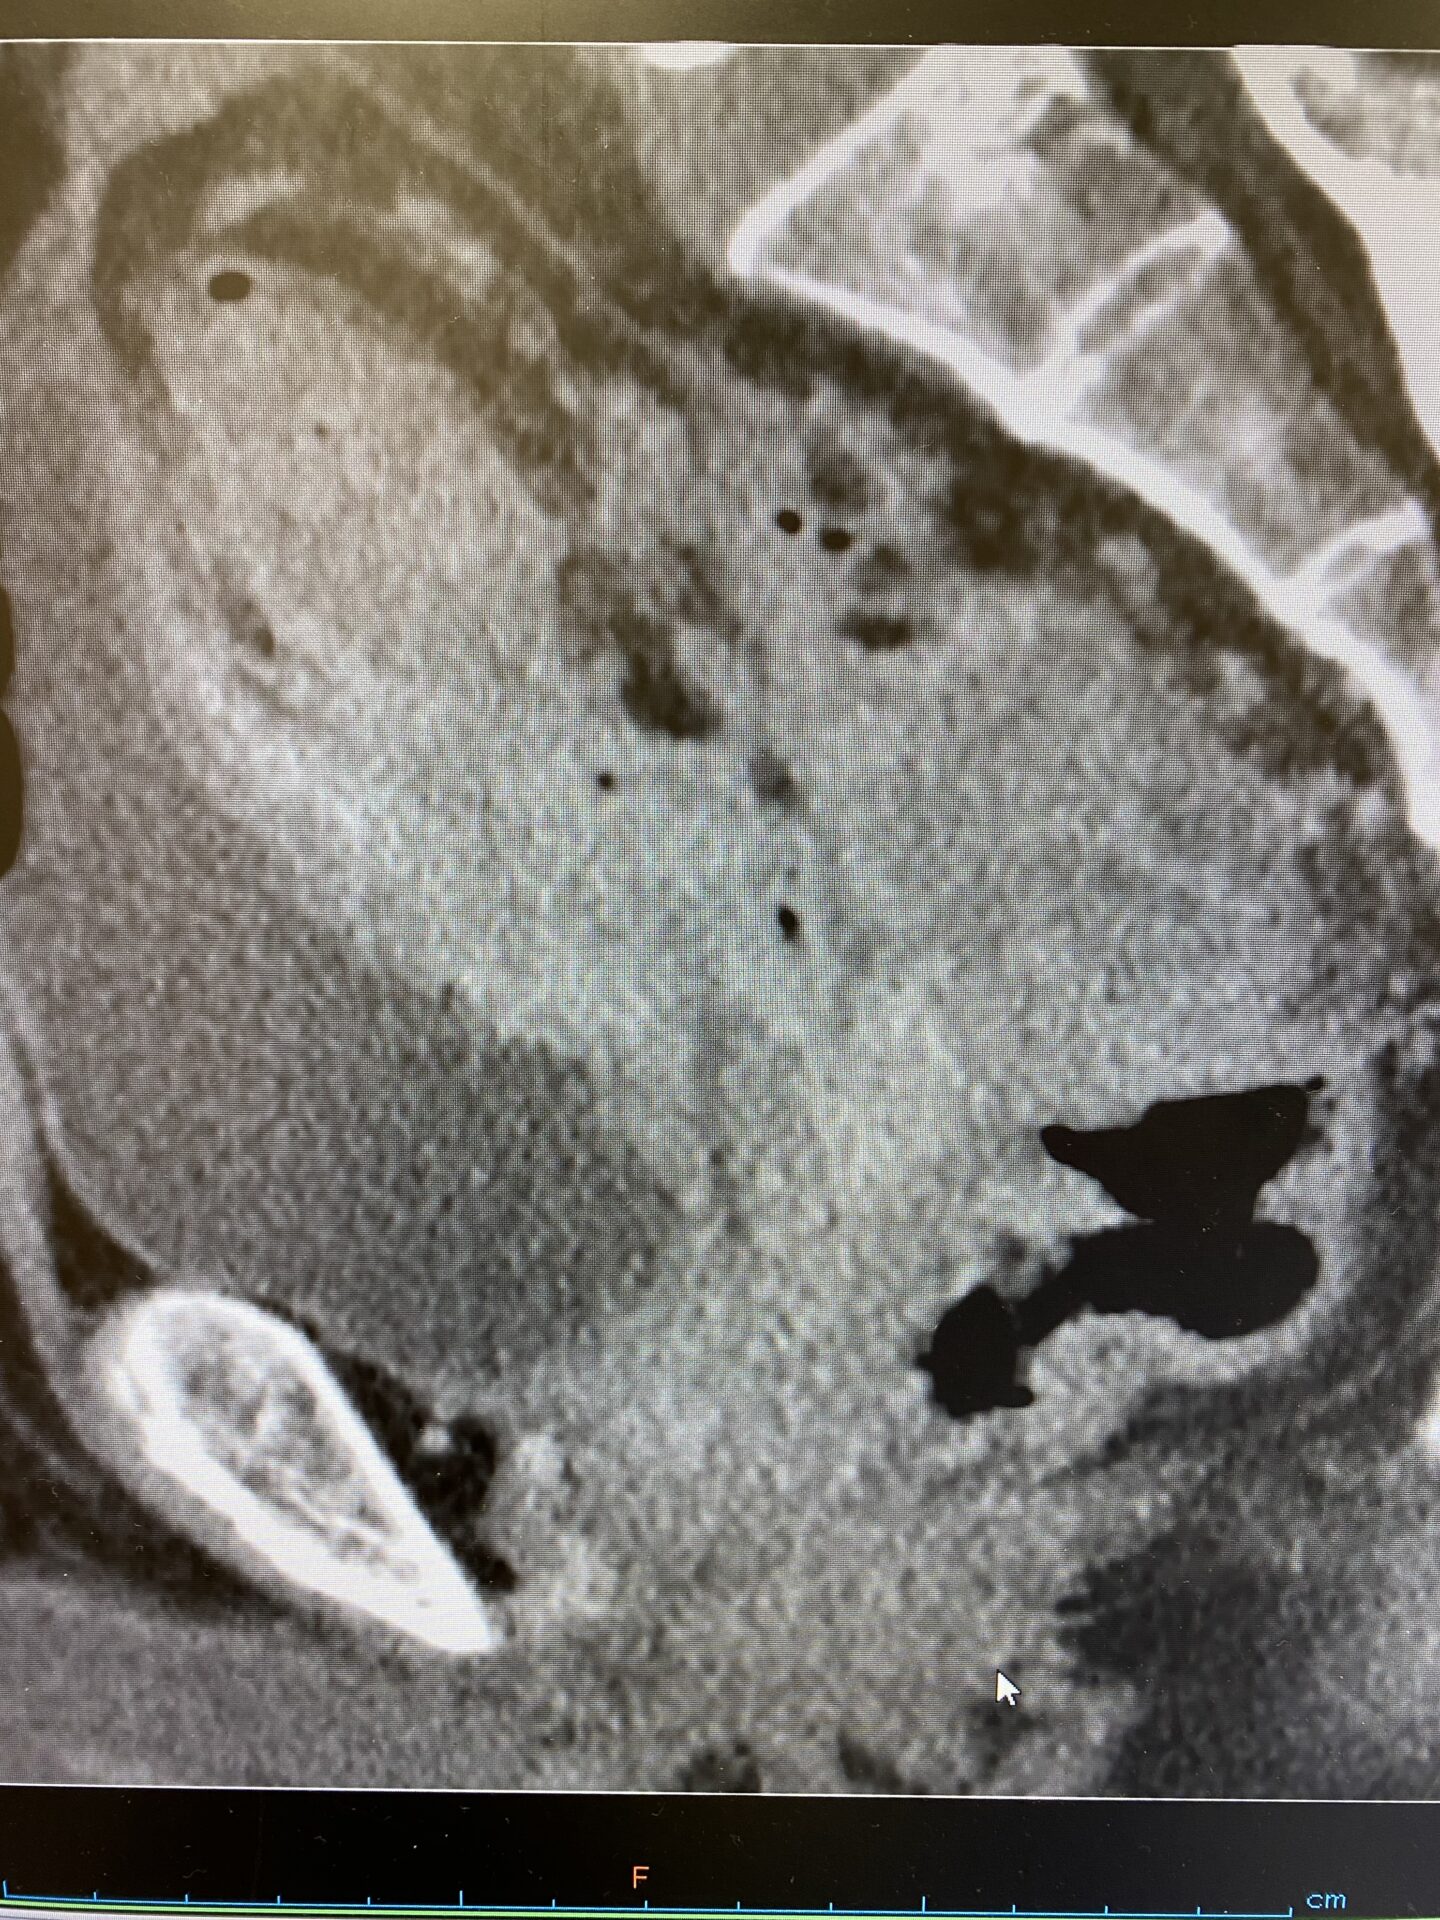

膀胱結腸瘻

先日、2週間前から夜間頻尿5回、尿意切迫感が出現しているとの事で当院に来院さ…